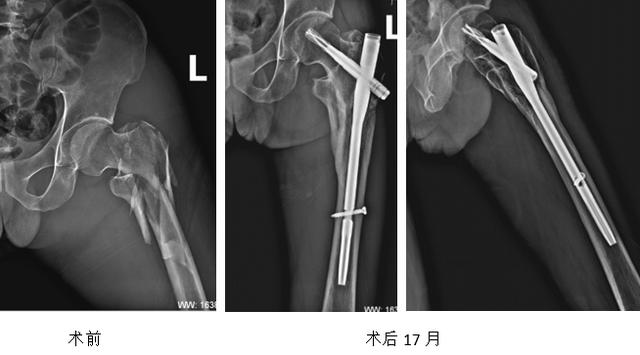

股骨转子间骨折术后失败

翻修术后一年